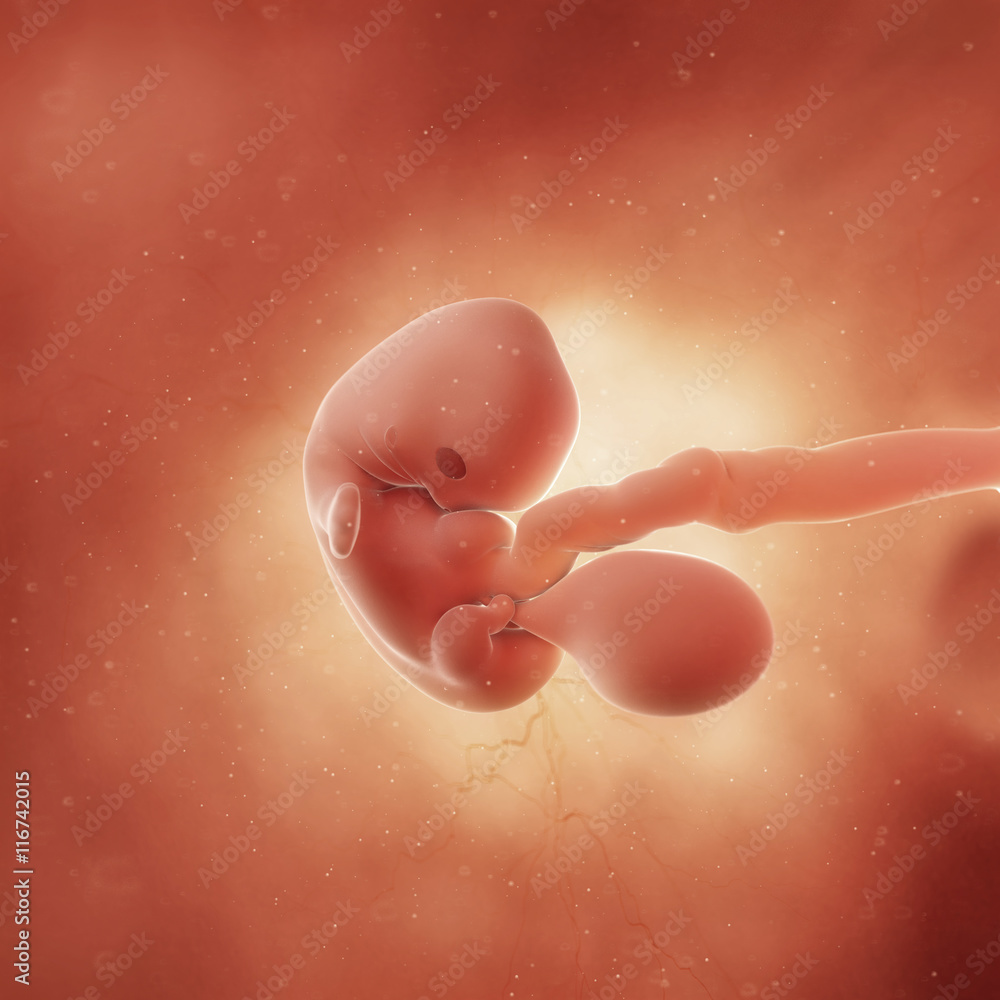

Эмбрион на 8 неделе беременности

Человеческий эмбрион на 8 неделе беременности

Эмбрион на 8 неделе беременности